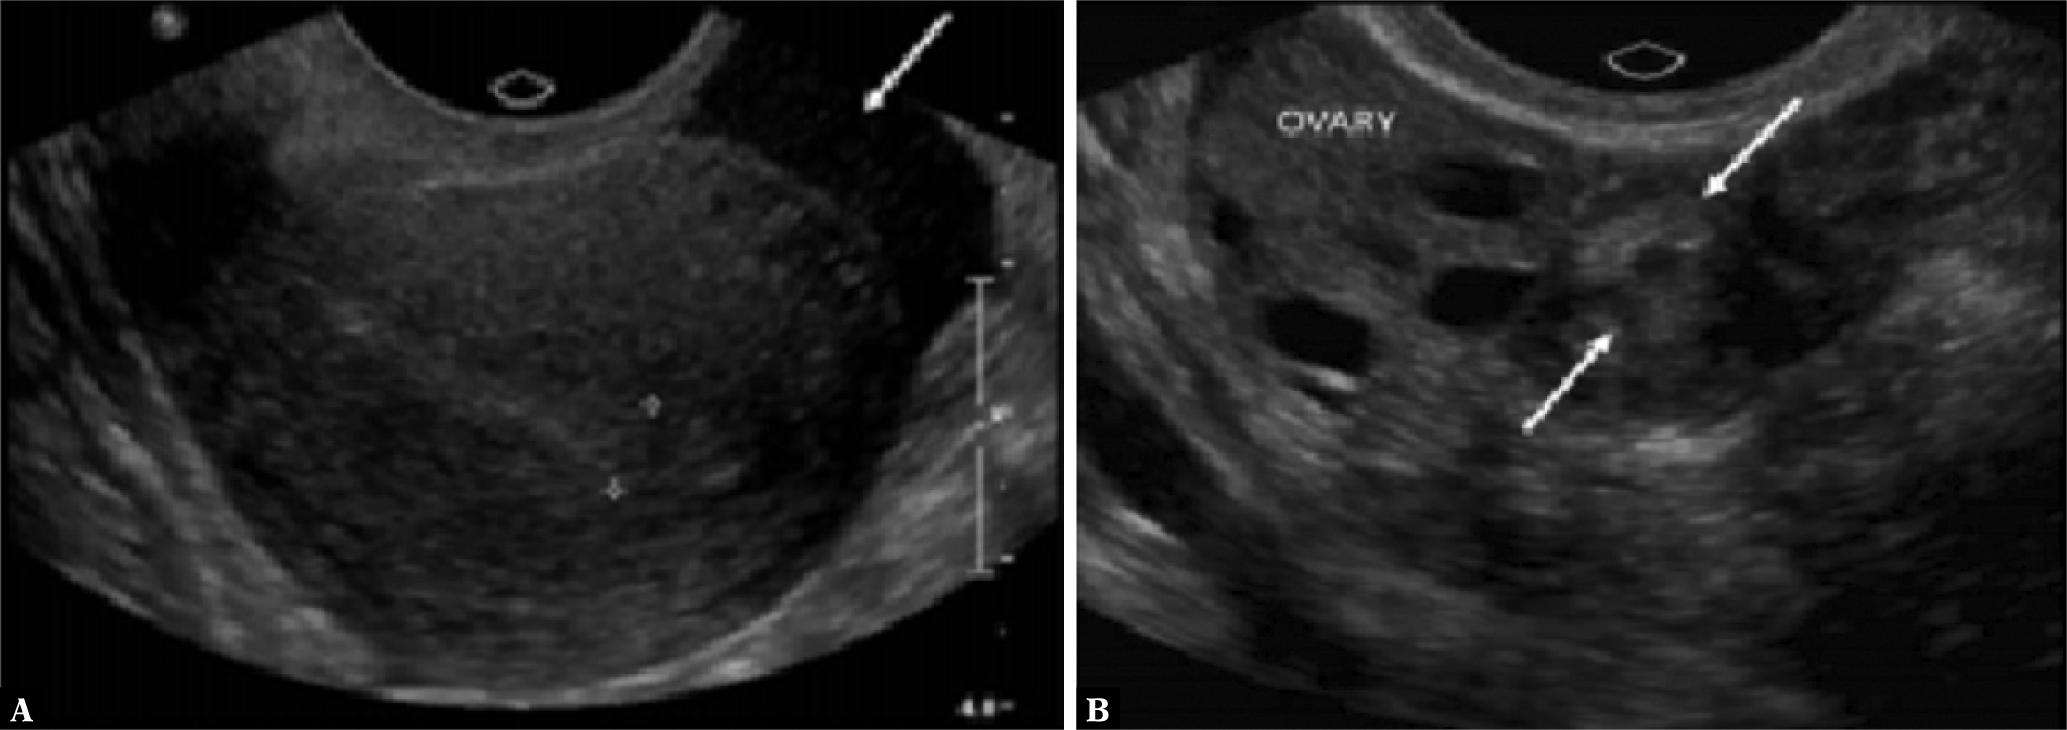

Fig. 2.